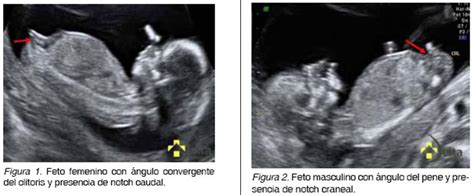

- Ecografía (Ultrasonografía): Verificación de marcadores del sexo fetal a partir de la 12ª semana de embarazo. La fiabilidad es mayor en fetos femeninos.